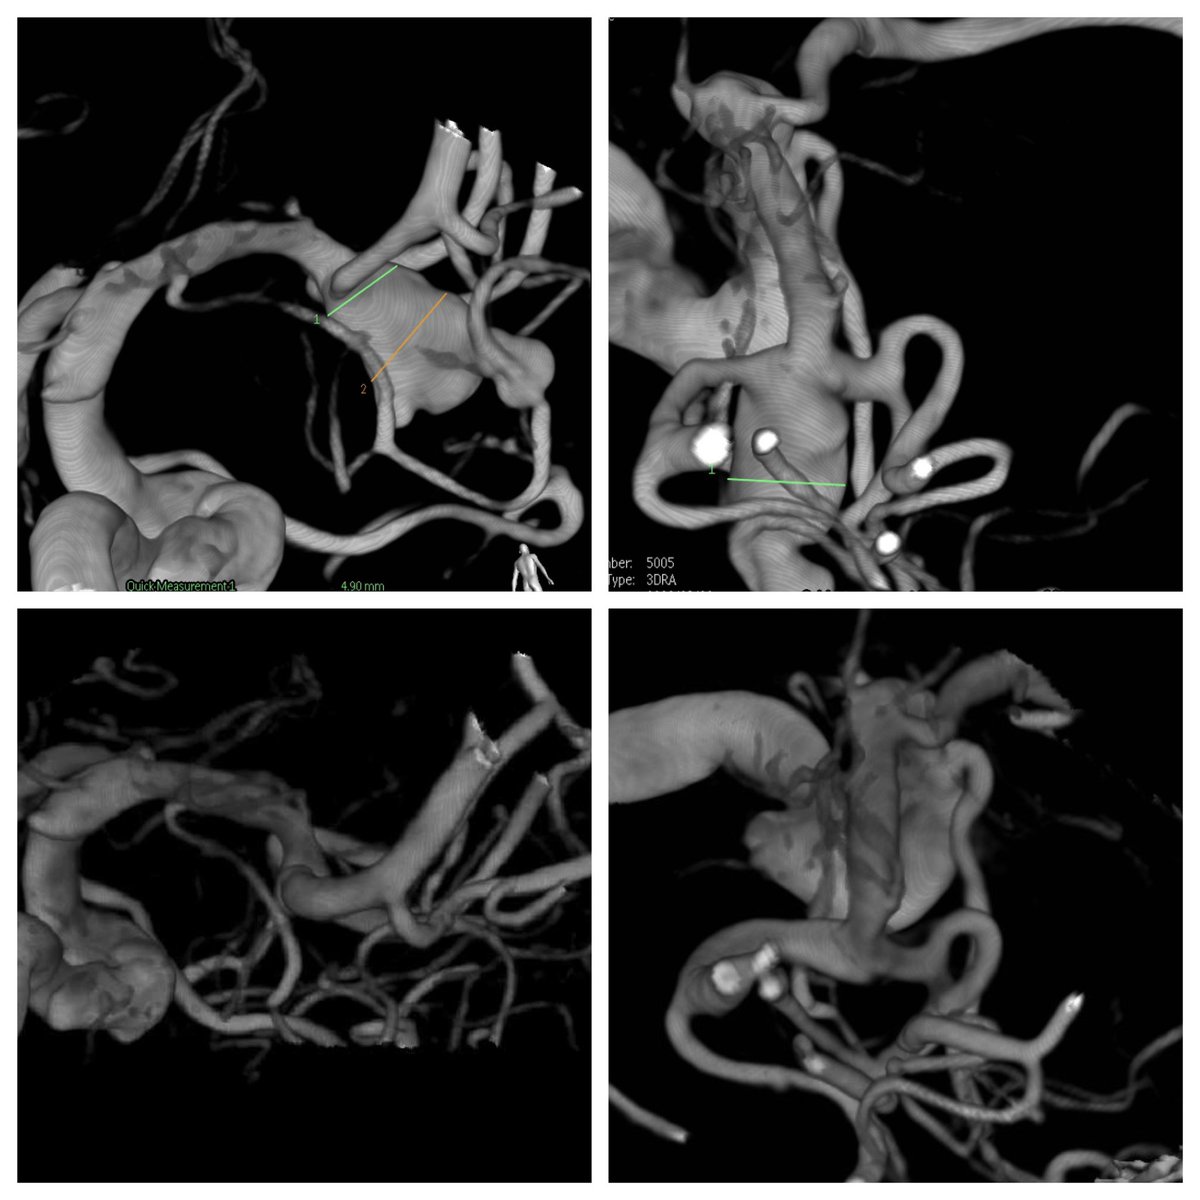

Large MCA Aneurysm w/ both branches arising from the sac + Calcified wide neck #Neurorad #NeuroIrad #neurosurgery #Neurointervention #radres #medtwitter #neurotwitter #meded World Medica How would you treat it??